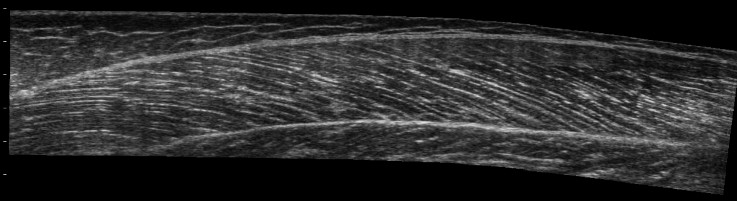

Thrilled to be an incoming TT-AProf in the Department of Human Physiology and Nutrition

@uccs @Johnson_Beth_El

World-class facilities and a great balance of teaching and research. I’ll remain active with @MHarrisLove1 and the rest of

@3maplab team @cuanschutz @CUPhysTher